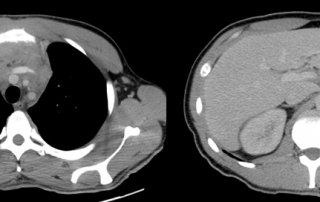

Clinique : Présence de sueurs nocturnes et douleurs dorsales basses récentes. Une adénopathie sus-claviculaire gauche. Discrète voussure latéro-sternale gauche.

Diagnostic de lymphome de Hodgkin classique sclérose nodulaire sur la biopsie chirurgicale d’une adénopathie sus-claviculaire gauche.

Hémoglobine 10.4 g/l, GB 12.4 G/L, lymphocytes 0.9 G/L ; albumine 33 g/l BM normale.

TEP-FDG après 2 cycles dans le cadre de l’essai AHL2011 avec relecture centralisée. Réponse métabolique complète (score 1 des critères de Deauville).

Le traitement est poursuivi par ABVD x 4 cycles selon l’essai AHL 2011.

Après 4 cycles (BEACOPP x 2 + ABVD x 2) évaluation par TEP-scanner : absence de foyer significatif au niveau médiastin et des lésions osseuses initiales, maintien de la réponse métabolique complète. Persistance d’une zone hétérogène du sternum correspondant à l’atteinte initiale (lésion non cible).

L’évaluation de fin de traitement (BEACOPP x 6 cycles + ABVD x 4 cycles) confirme la rémission complète, avec image stable du sternum.